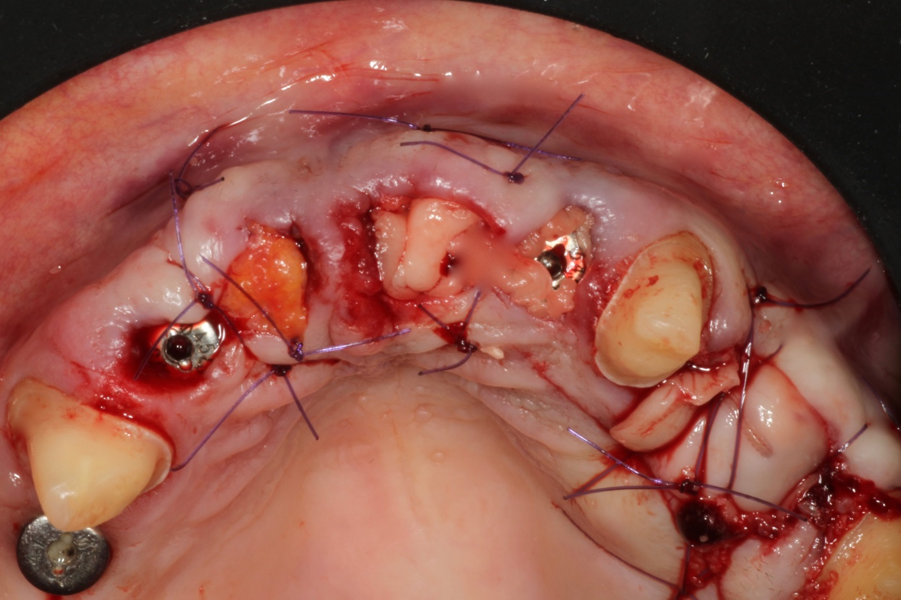

Both surgical interventions were performed under local anaesthesia, and antibiotic medication (a single dose of 2 g of amoxicillin) was administered 60 minutes before surgery. The first stage of rehabilitation of the maxilla involved immediate implant placement in the post-extraction sockets of both lateral incisors in combination with the socket shield technique for the right lateral incisor. Owing to an increased tooth mobility of more than Grade II, the socket shield technique was contra-indicated for the left lateral incisor and both premolars. The clinical crowns of both central incisors were decapitated, and the roots were carefully prepared with a round diamond bur under rinsing with sterile saline solution, until both cranial root edges reached a distance of 3 mm from the gingival margin (Fig. 5). In the right lateral incisor site, a socket shield was prepared as described by Gluckman et al.12 The extracted premolars were mechanically cleaned and then dried and processed with the Smart Dentin Grinder (KometaBio) according to the manufacturer’s recommendations.13 After implant site preparation, particulate dentine was applied into the prepared left lateral incisor implant site, and both extraction sockets of the left premolars (Fig. 6). Implant placement was performed in the extraction sites of both lateral incisors with two BEGO Semados RSX implants (BEGO Implant Systems) with a length of 13.00 mm and a diameter of 3.75 mm (Fig. 7). Peri-implant gaps were grafted with particulate dentine autograft and sealed with platelet-rich fibrin (PRF) membranes using the Poncho technique.14 After buccal and palatal tunnel preparation, the premolar extraction sockets and submerged left central incisor root were covered with PRF membranes, prepared according to the Choukroun method (A-PRF, mectron) after centrifugation at 1,300 rpm for 13 minutes.15 The right central incisor was covered with a connective tissue graft harvested from the palatal mucosa of the first quadrant. Covering membranes and the connective tissue graft were introduced into the buccal and palatal tunnel preparations and fixed with absorbable monofilament #5/0 suture thread (Serafast, Serag Wiessner; Fig. 8). The postoperative radiograph showed adequate root submersion of the central incisors, correct implant positioning in the lateral incisor sites and proper filling of both premolar extraction sockets (Fig. 9). The patient was provided with the fixed provisional bridge (Fig. 10) and prescribed amoxicillin (1 g three times a day for five days after surgical intervention). Postoperative healing was uneventful.

Fig. 5: Clinical situation after partial extraction of tooth #12, extraction of tooth #22, and root submersion of teeth #11 and 21.

Fig. 6: Clinical situation after extraction of teeth #24 and 25 and augmentation with autologous dentine.

Fig. 7: Immediate implant placement into the fresh extraction socket of tooth #22 after ridge grafting with autologous dentine.

Fig. 8: Clinical situation after completion of first-stage surgery.